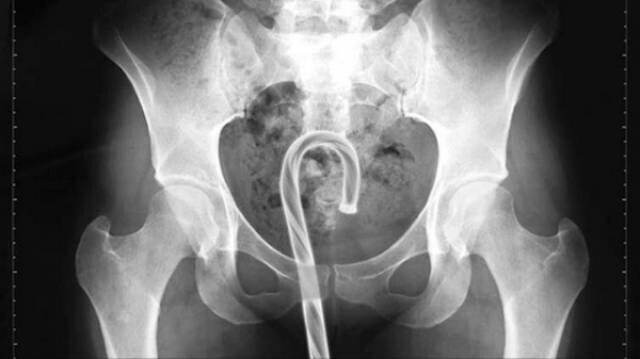

4. Карамельна тростина